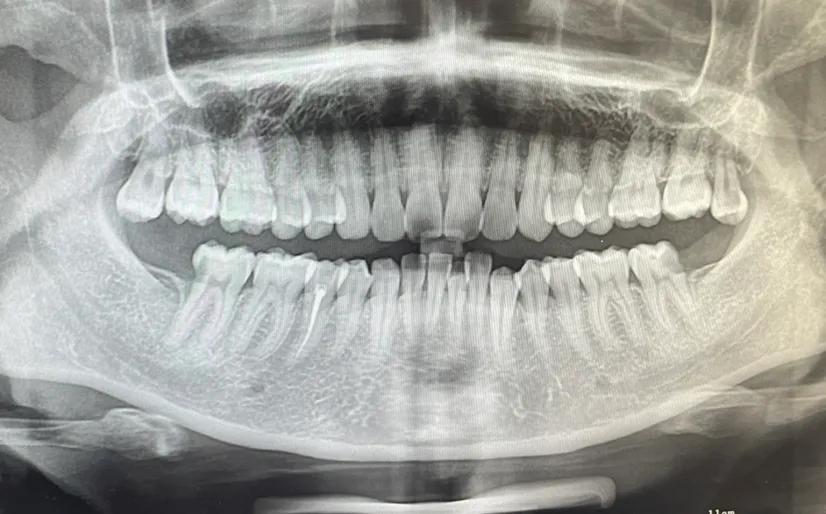

拓展知識(shí):種植牙中間一般要拔多少顆

這個(gè)要根據(jù)患者的實(shí)際情況,不同的患者能承受的不同 。建議到正規(guī)口腔科醫(yī)院【北京三級(jí)口腔醫(yī)院】根據(jù)患者的情況在決定。患者可以在恢復(fù)牙齒咀嚼功能的前提下兼顧牙齒美觀,針對(duì)全口牙齒缺失的患者是可以通過(guò)全口種植來(lái)恢復(fù)牙齒功能與美觀的,種牙點(diǎn)擊申領(lǐng)種牙補(bǔ)貼

傳統(tǒng)種植牙方式需要二次手術(shù)和3-6個(gè)月修復(fù)期,這對(duì)于怕麻煩追求率的市民或許不太合適,可選擇“即拔、即種、即用”的用種植方案,該技術(shù)是英國(guó)愛(ài)丁堡大學(xué)贊安南博士帶領(lǐng)實(shí)施的,根據(jù)患者牙槽骨密度、高度、寬度,自動(dòng)避開(kāi)血管和神經(jīng),以1微米的精度種植牙根,做到即拔即種,一次完成手術(shù)。

一般連續(xù)牙齒缺失的情況是可以進(jìn)行一次種植牙修復(fù)的,并且不需要種植多顆種植體,一般需要連續(xù)缺失5顆或者4顆牙,只需要2到3個(gè)種植體就足夠,在費(fèi)用上也省了不少錢,如果有需求一定要選擇正規(guī)專業(yè)點(diǎn)的口腔機(jī)構(gòu)進(jìn)行缺失牙種植調(diào)節(jié)。

一次可以種植2到3顆,但拔牙一次只能拔一顆,等徹底消炎好了才能拔第二顆。

看什么情況才能做決定,正常能做3顆牙左右,特殊情況滿口牙一起種。